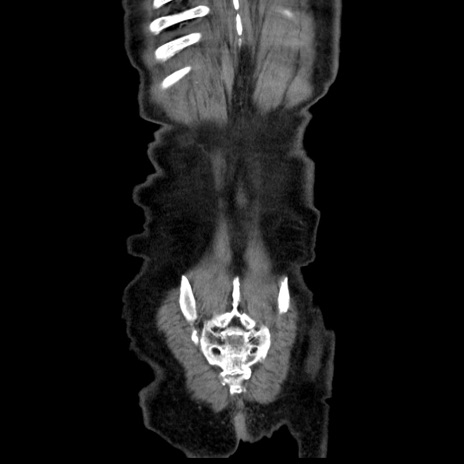

横断像